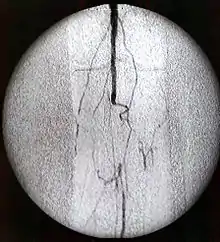

Los contrastes radiológicos son sustancias radiopacas, que aplicadas por diferentes vías de administración (oral, rectal, endovenosa, etc.) pueden ser empleadas, durante un examen de rayos X o radiografías, para facilitar y/o mejorar la visualización de distintos órganos o fluidos de nuestro cuerpo con un fin diagnóstico. También se emplean contrastes radiológicos para las técnicas de resonancia magnética.

Contrastes radiológicos yodados

Se trata del grupo más importante dentro de los medios de contraste, ya que son los más usados. Se caracterizan por una alta densidad de contraste y una baja toxicidad.